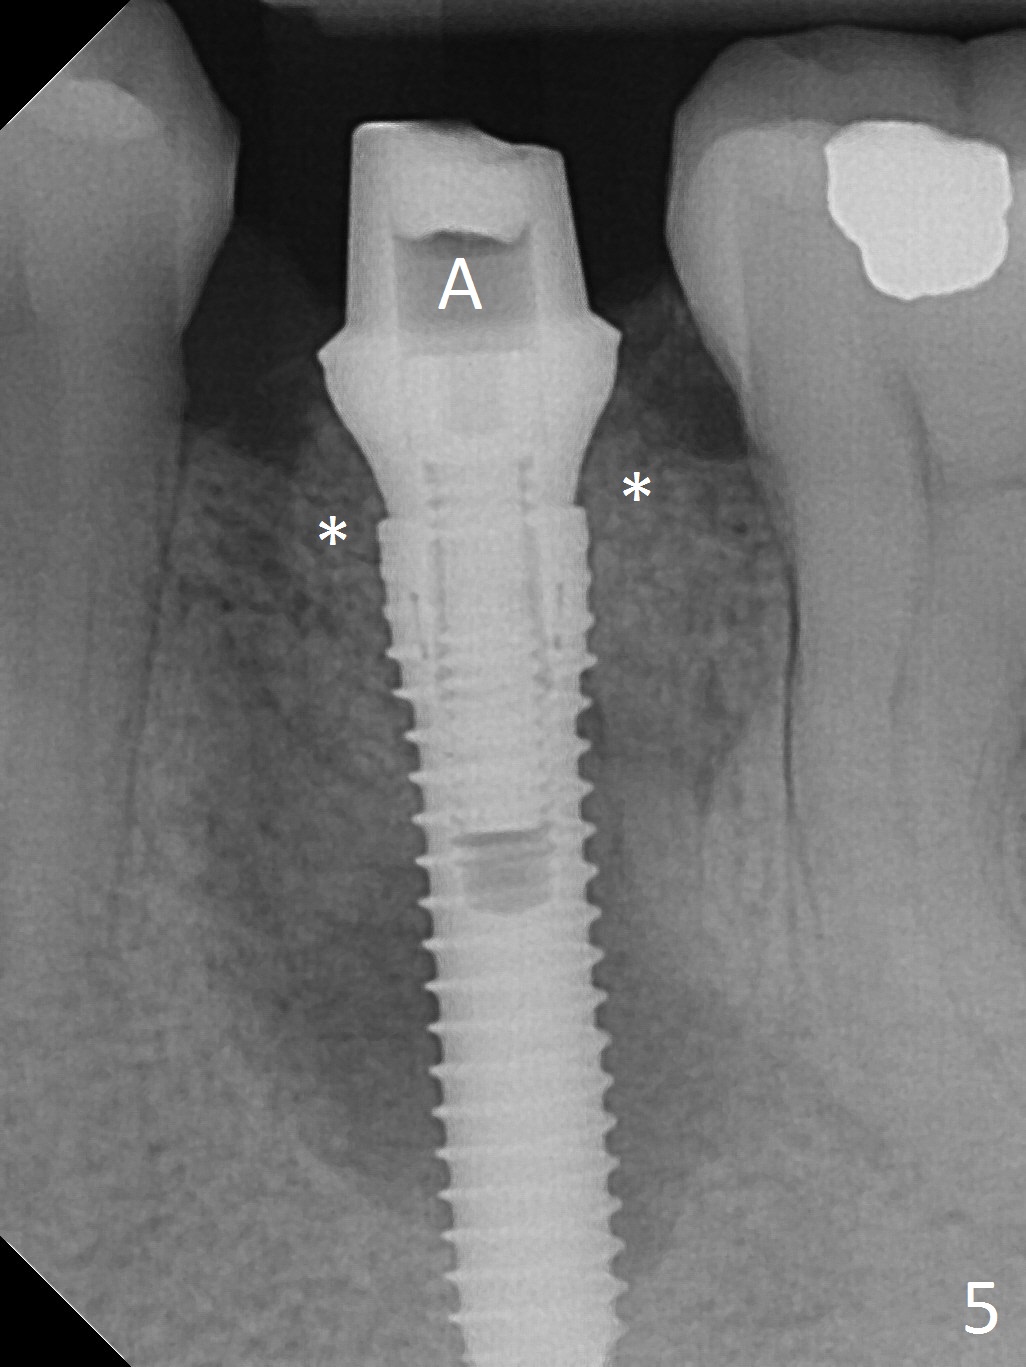

Extraction of the lower left 2nd premolar with vertical fracture (Fig.1,2 >) is easy because of peri-radicular radiolucency. The apical end of the osteotomy is not shown with a 2 mm pilot drill (Fig.3) or a 3.8x18 mm implant (Fig.4) in place. It appears that the implant is not placed deep enough. Following 3-4 more turns of the implant and placement of a 5.5x4(3) mm abutment (Fig.5 A), allograft is placed (*). A postop panoramic X-ray is taken (Fig.6); the osteotomy could have been deepened to reduce the possibility of periimplantitis. Retrospectively, the panoramic X-ray should be taken after use of the pilot drill. The bone around the implant appears to have regenerated 4 months postop (Fig.7,8). Bone density appears to continue increasing 9 months postop (i.e., 4.5 months post cementation, Fig.9). Bone loss is minimal 2 years post cementation (Fig.10).